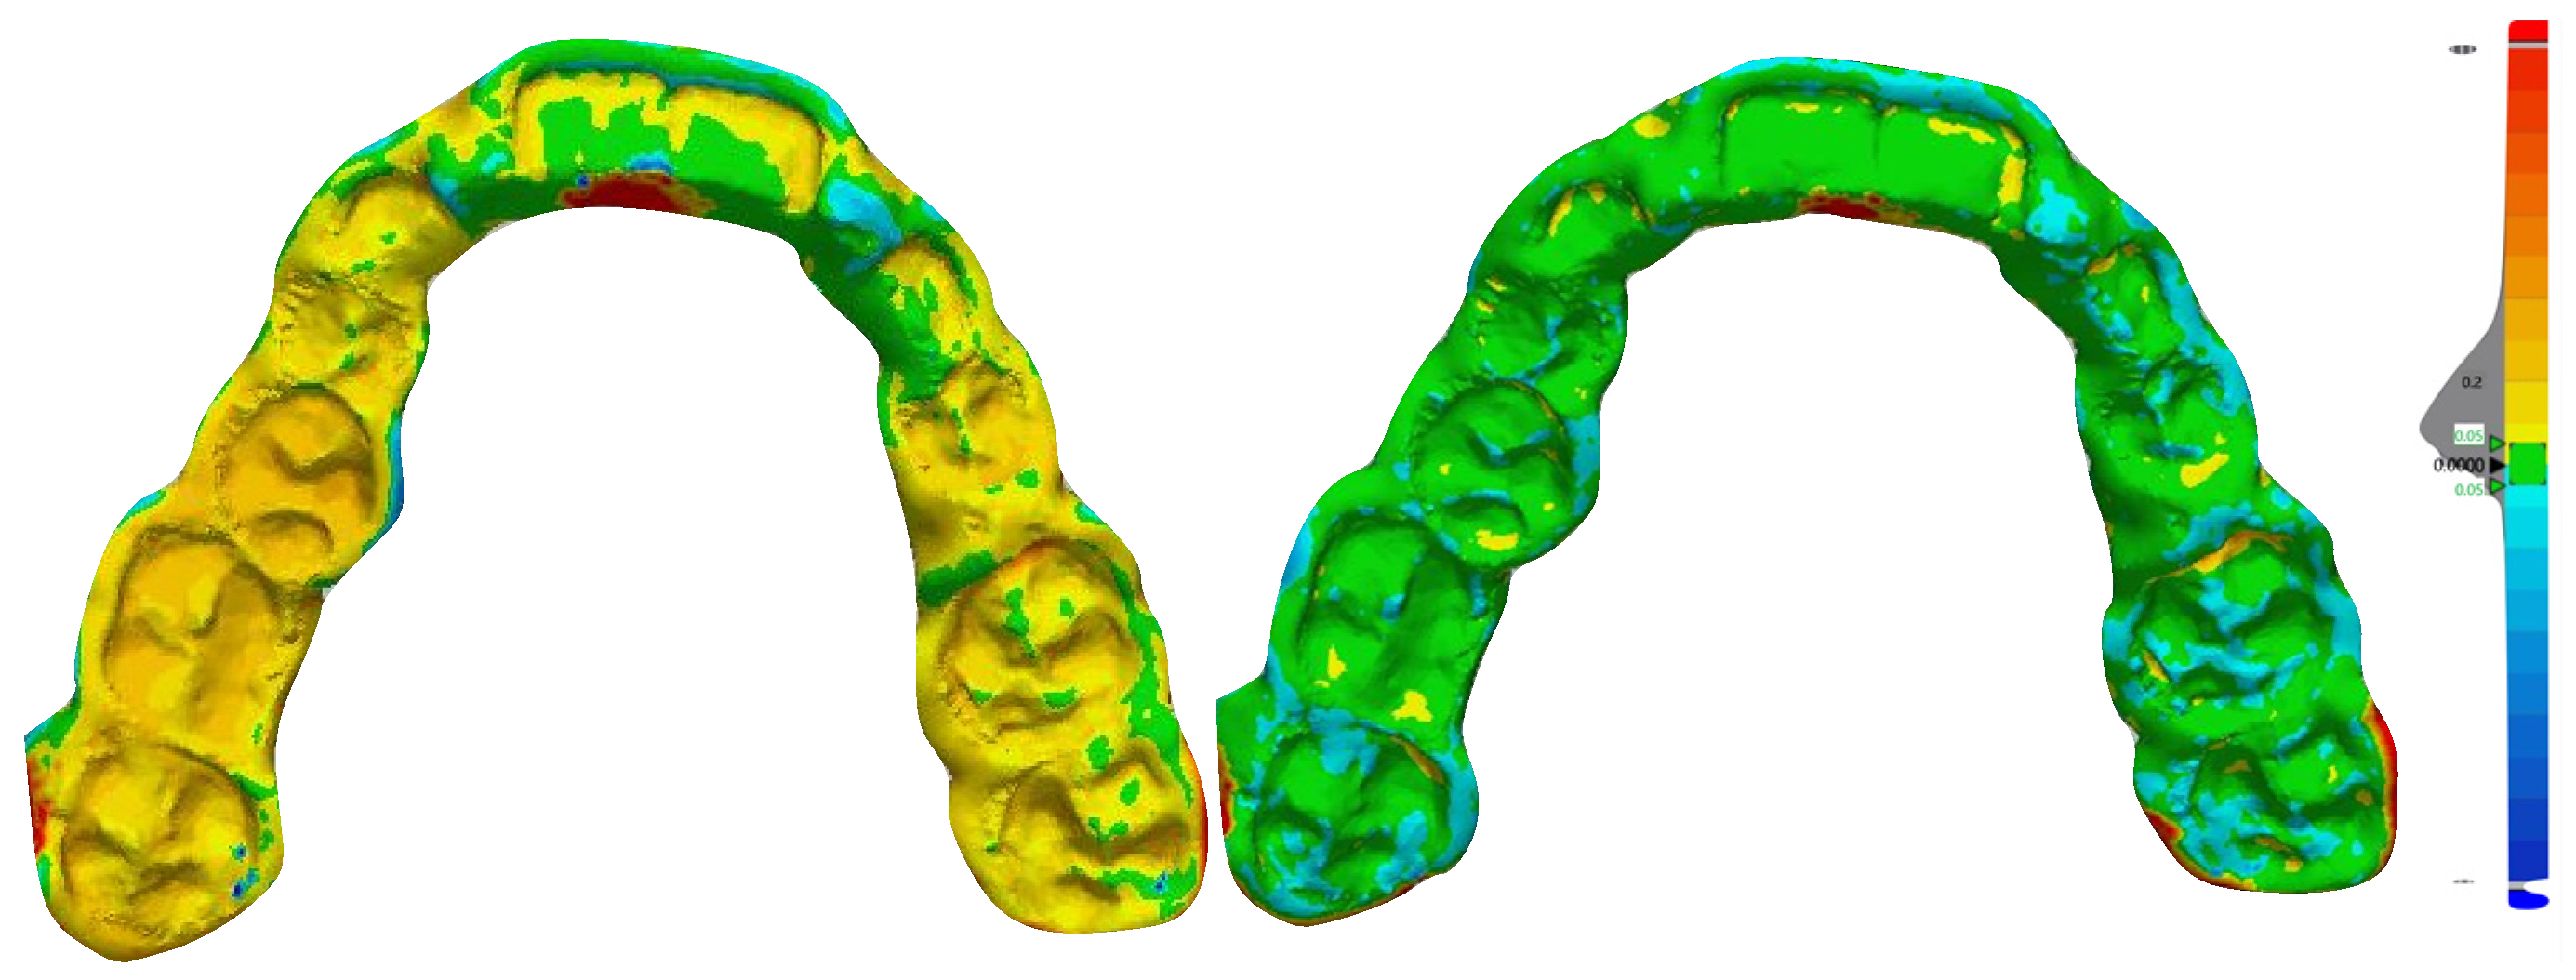

| Prototyped | 10 | 0.20 mm ± 0.018 | p < 0.001 |

| Milled | 10 | 0.31 mm ± 0.021 | |

| Prototyped | 10 | 95.66 ± 1.19 | p < 0.001 |

| Milled | 10 | 66.99 ± 1.38 | |